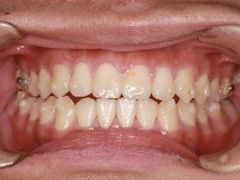

• -精德口腔·种植修复·儿牙中心(财富中心店)

姗姗来迟223 | 23-12-15

报错